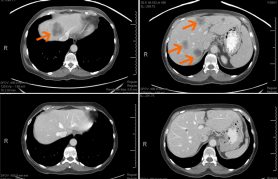

Los resultados clínicos del ensayo se informaron en la reunión anual de la American Society of Clinical Oncology (Sociedad Estadounidense de Oncología Clínica) en junio. De 37 pacientes con respuestas evaluables, dos tuvieron respuesta completa, siete tuvieron respuesta parcial y 17 tuvieron la enfermedad estable. Estos números suman una tasa de control del 70% y un índice de respuesta general del 24%. La mediana de la duración de la supervivencia sin progresión fue de 3.9 meses.